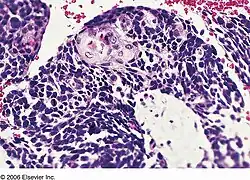

![]() | |

| Combined small cell lung carcinoma containing a component of squamous cell carcinoma | |